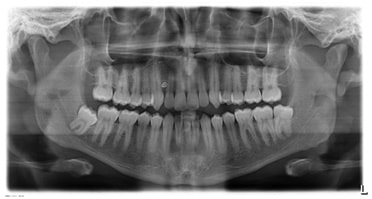

Radiografias Panorâmicas

Radiografias Digitais com Laudos e Análises